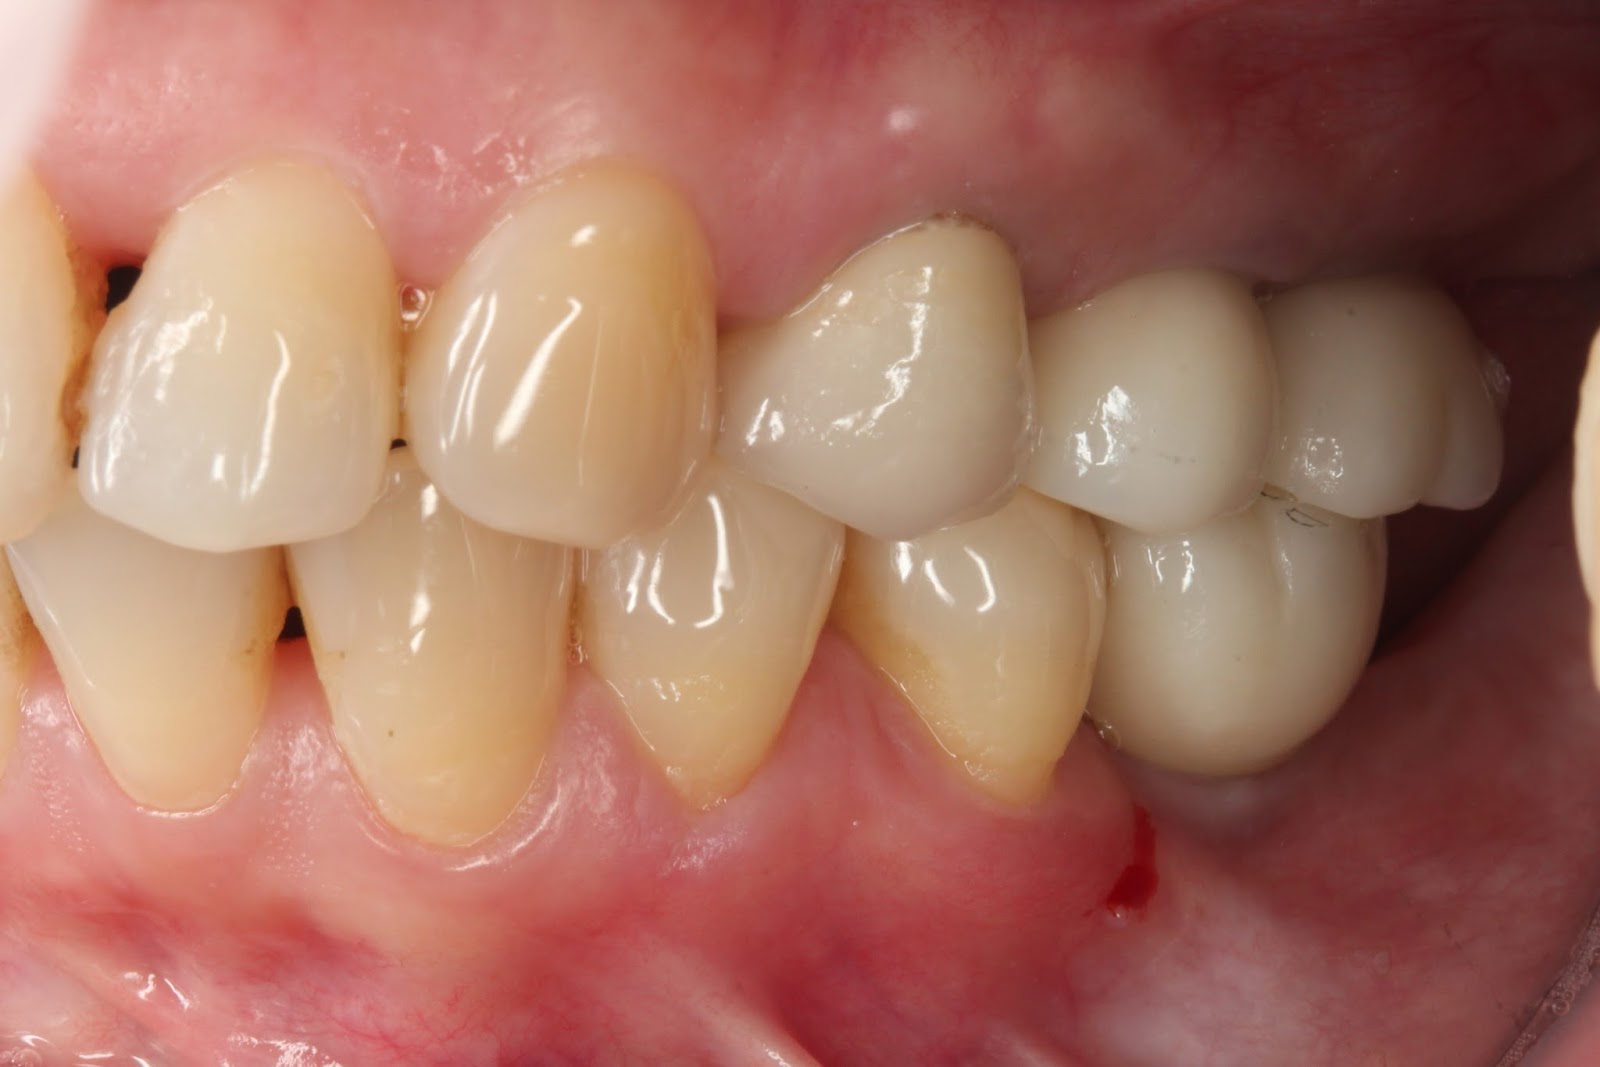

手術過後四個月,我們按部就班,完成最終全鋯冠與全瓷冠假牙部分。回想起整個病例的過程,手術部分真的是超級大的壓力,幸好老天保佑,一切都依照計畫順利進行,病友們也得到最滿意的結果。一次次看到自己滿意的結果,老天爺真的是有保佑,希望後續病友們定期檢查,就當作好朋友們聊聊天,問候一下感覺到溫暖而親切的醫病關係。

治療後右側穩定咬合

治療後左側穩定咬合